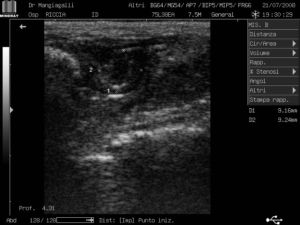

Ecografia pelvica - In alto vescica (anecogena e ben delimitata), immediatamente sotto il fondo regolare dell'utero (ipoecogeno). 19\07\2008 |

Ecografia pelvica - Vescica regolare (in alto a sinistra); in alto a destra fondo uterino con cavita endometriale appena delimitata. 21\07\2008 |

Un'ecografia, fatta subito dopo il parto aveva evidenziato un utero

compatibile con il puerperio normale, ma la comparsa, successiva, di secrezioni

vaginali purulente, seppure scarse faceva prendere in considerazione l'ipotesi

di una endometrite purulenta: la piometra.

| Ecografia pelvica - Ben evidente la cavità uterina. 05\08\2008 |

La diagnosi è stata confermata da una successiva ecografia che ha evidenziato un utero ingrossato, con materiale ipo\anecogeno nella cavità endometriale (pus) e miometrio ipoecogeno; gli esami ematici hanno rilevato una caratteristica leucocitosi.